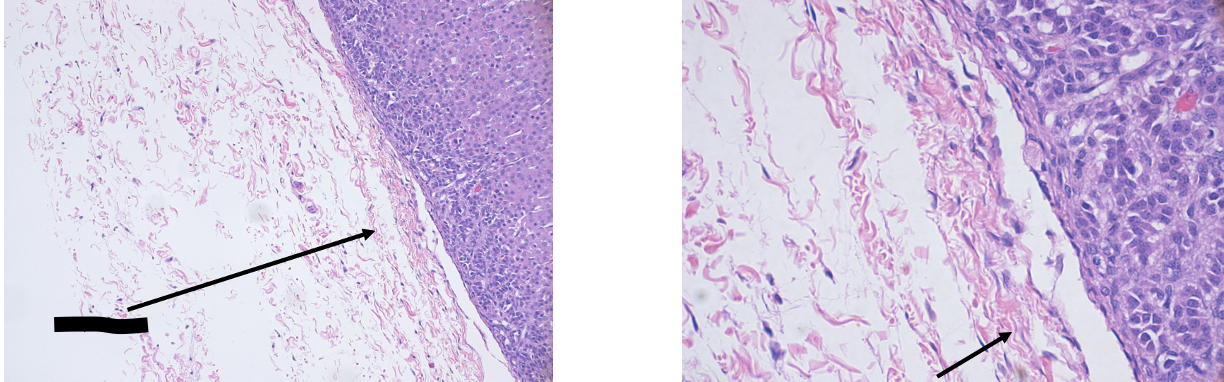

Chromophobes –> black arrows

Basophils –> red arrows

Black arrows = pituicytes